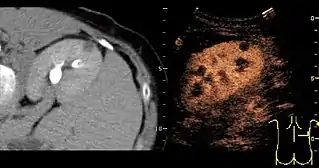

Solid malignant tumors in the kidney do not exhibit specific enhancement patterns like some liver lesions, and no valid enhancement criteria between benign and malignant renal lesions have been proposed. However, CEUS is used in some patients after ablation of renal cell carcinoma to evaluate contrast uptake in the treated area (Figure 30).

Image fusion of ultrasound with a previously recorded dataset of CT or other modalities is rarely used in renal US. Reports on image fusion using CEUS or US combined with CT or MRI in the examination of renal lesions and in difficult US-guided renal interventions have been published (Figure 31). However, no recommendations have been published so far.[1]

Figure 31. Unspecific cortical lesion on CT is confirmed cystic and benign with contrast-enhanced ultrasound (CEUS) using image fusion.[1]

Figure 31. Unspecific cortical lesion on CT is confirmed cystic and benign with contrast-enhanced ultrasound (CEUS) using image fusion.[1] Figure 32. Strain elastography of a normal kidney. Red depicts soft areas, and blue depicts hard areas relative to the entire elastography image. Note that the medulla is softer than the cortex. A color bar is shown to the left of the image, where "S" and "H" denote soft and hard tissue, respectively.[1]